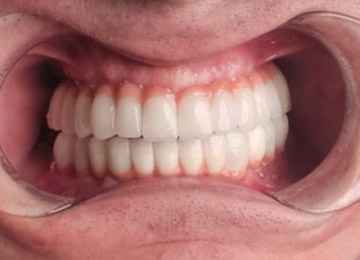

Имплантация зубов: фото "До" и "После"

All-on-4

All-on-6